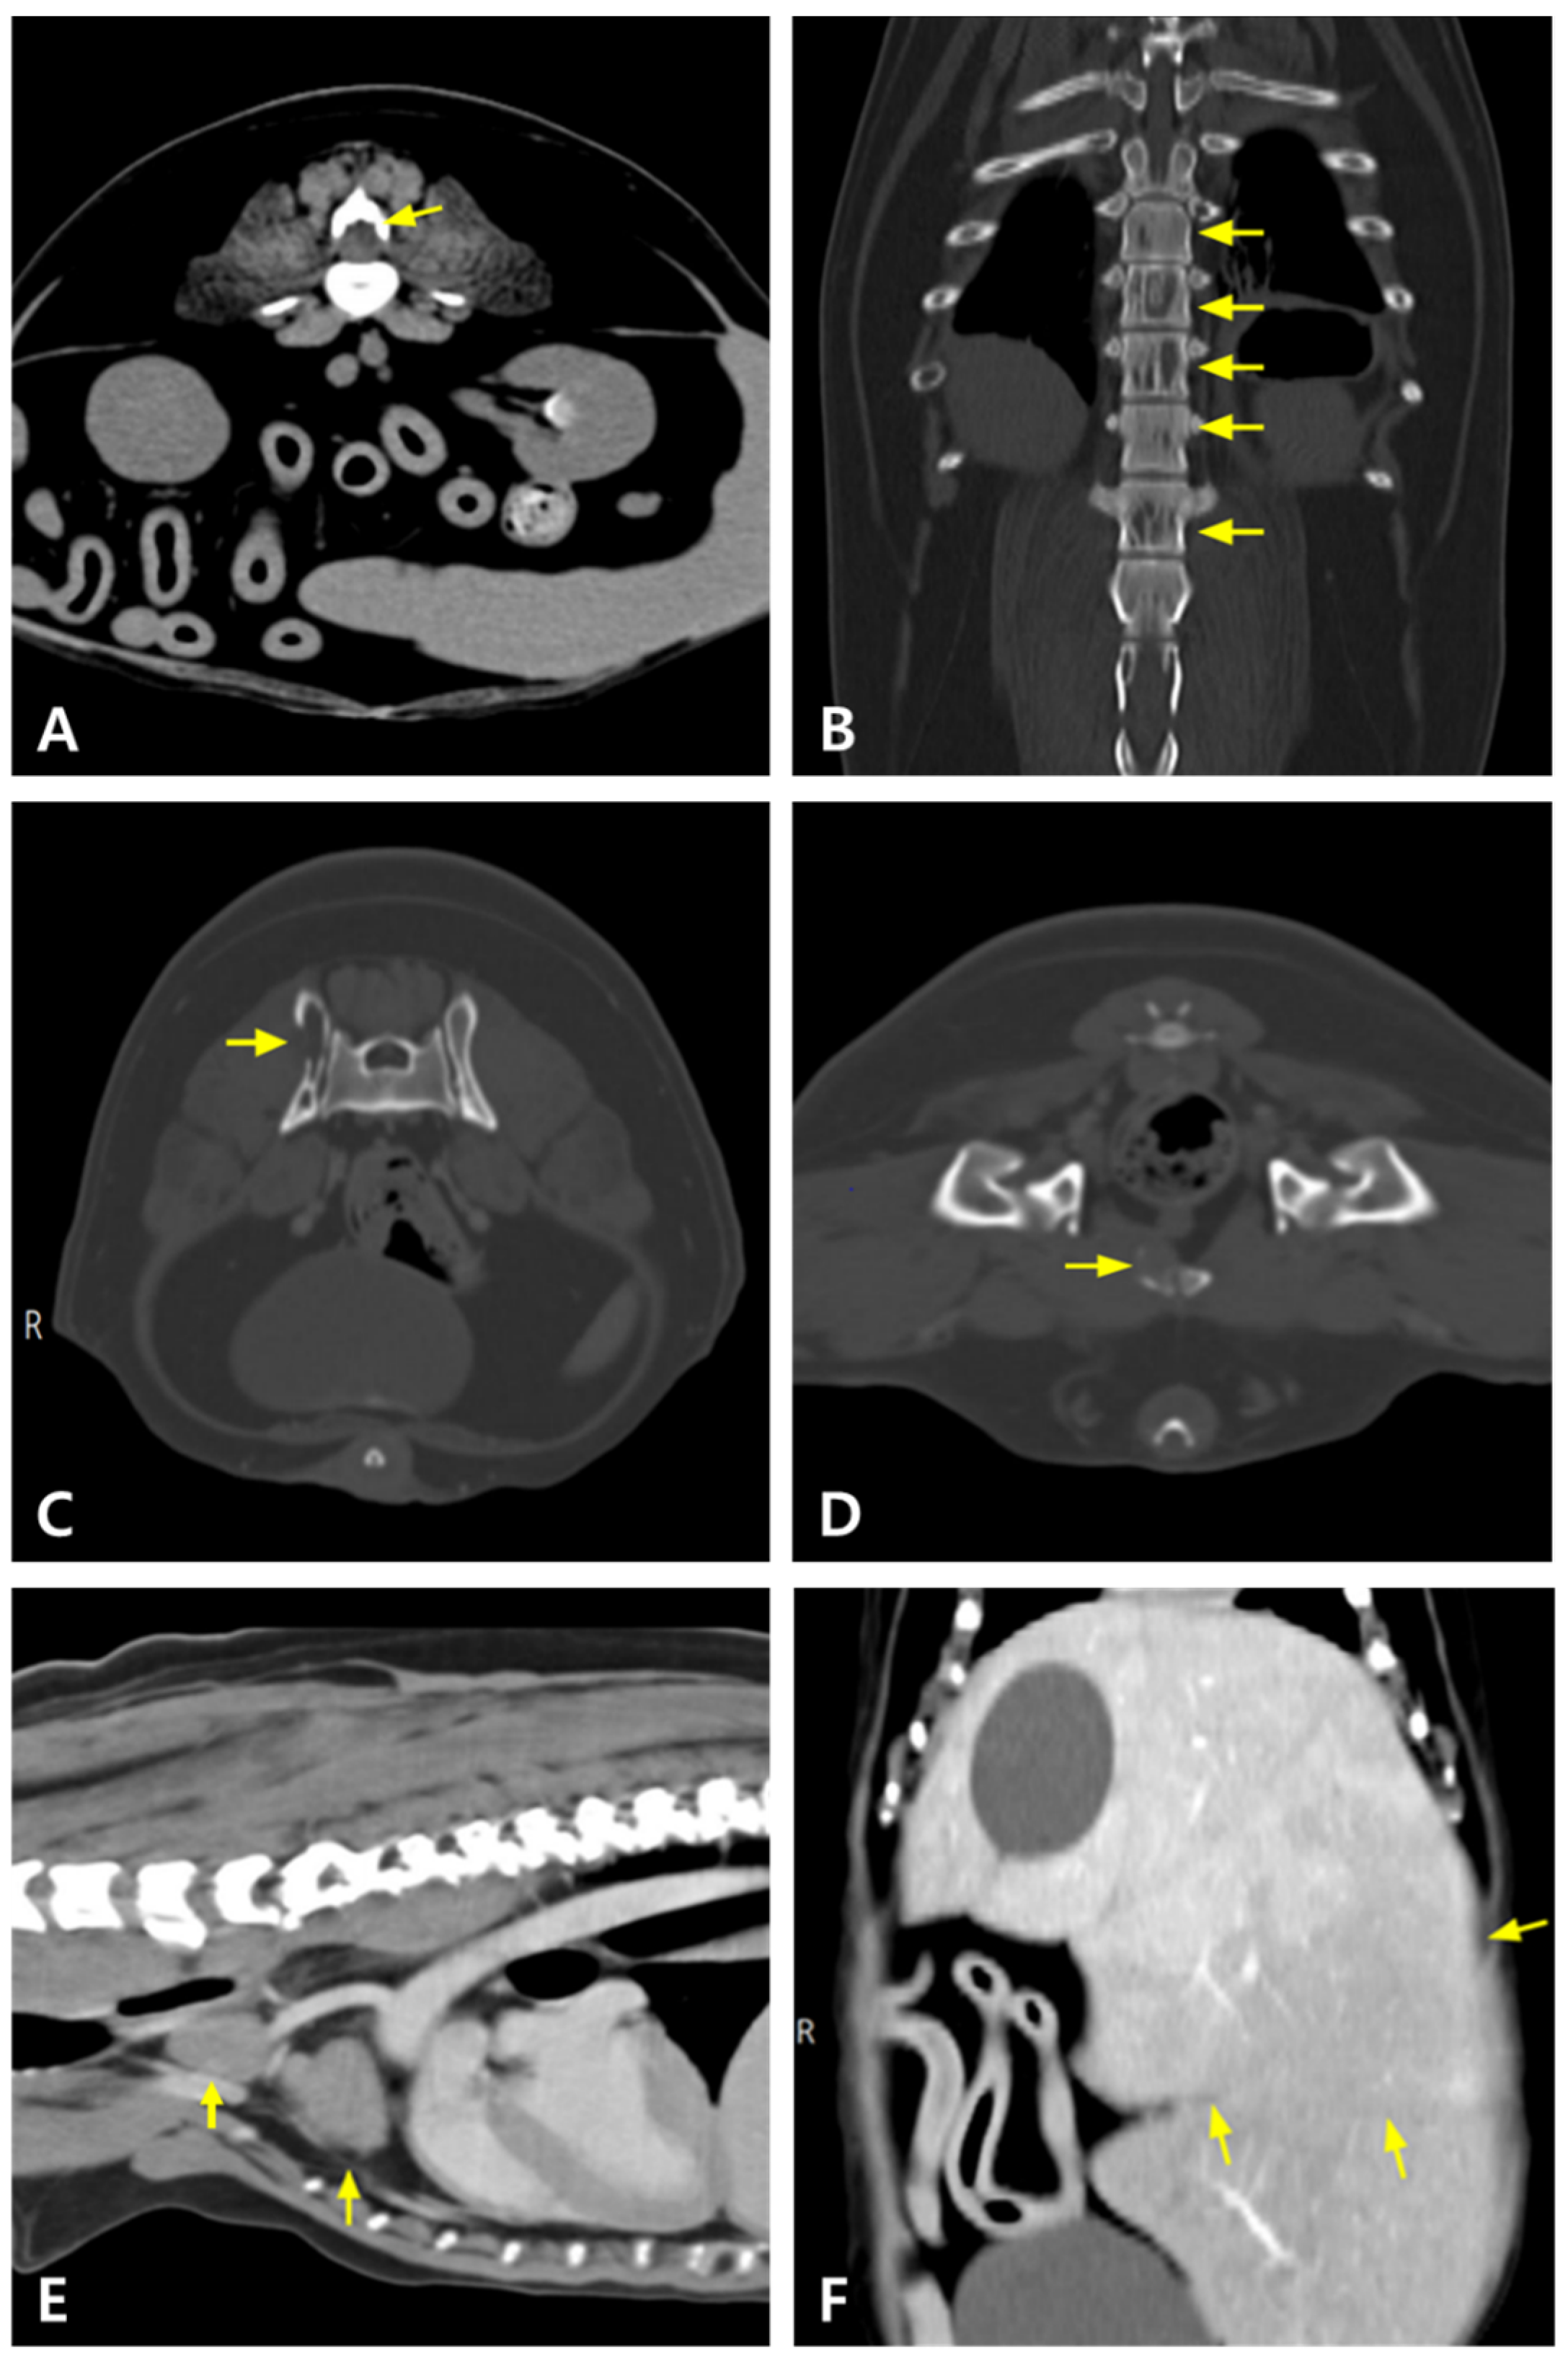

2. Case Description